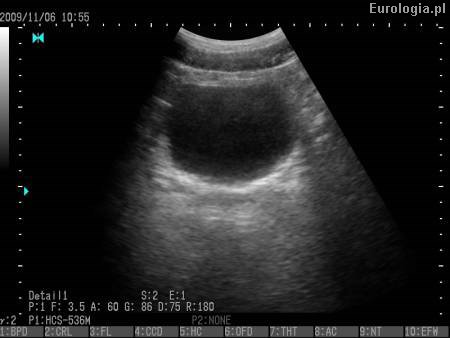

Fot. Prawidłowy pęcherz moczowy w badaniu USG.